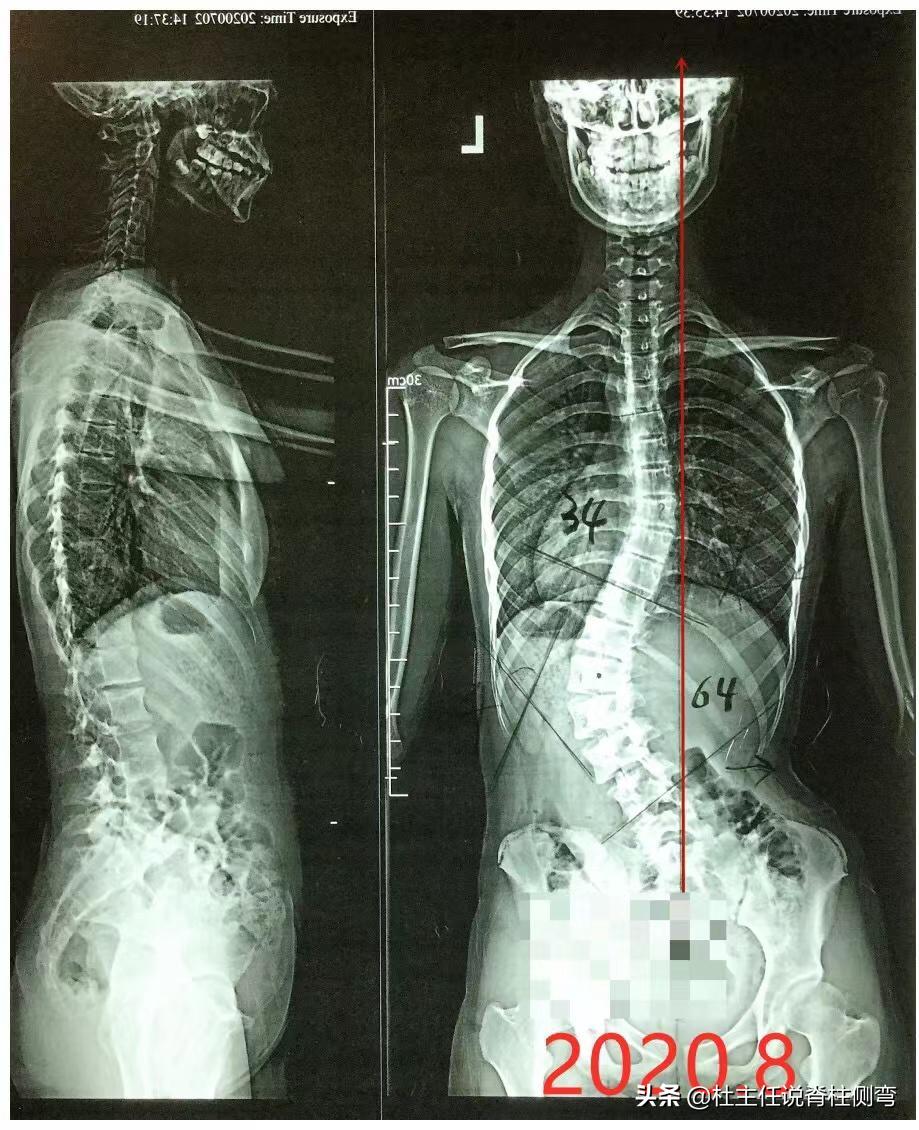

孩子在重新拍片后我们发现,她的度数较前增加, 胸弯Cobb约34°,腰弯Cobb约为64° ,体查发现 左下腰隆起约26° 。从片子中可以看到孩子的骨龄约为4级,处于生长发育的高峰期,通过计算风险系数为3.25,恶化的风险很高。

就这样坚持佩戴支具和训练5个月后,2021年5月份脱支具4-6小时拍片复查, 胸弯由34°减至28°,腰弯由64°减至50°,左下腰隆起由26°减至12° ,双侧腰线较前对称明显。